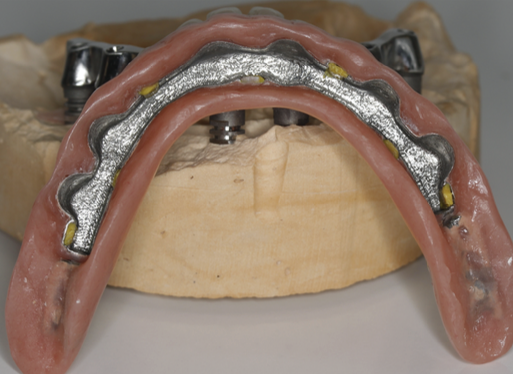

Proteza stă pe bară fără să se miște deoarece în baza protezei există elemente de ancorare siliconate de culoare galbenă așezate aproape una de cealaltă pe toată suprafața bazei (Fig. 3.9.14). Acele elemente creează fricțiune între proteză și bară și nu permite desprinderea involuntară a acesteia, chiar dacă pacientul mestecă alimente lipicioase. Proteza poate fi îndepărtată cu mâna doar printr-o acțiune voluntară a pacientului. Acest tip de lucrare reface funcția masticatorie, pacienții bucurându-se de toate tipurile de alimente fără grija că proteza va cădea sau va sări.